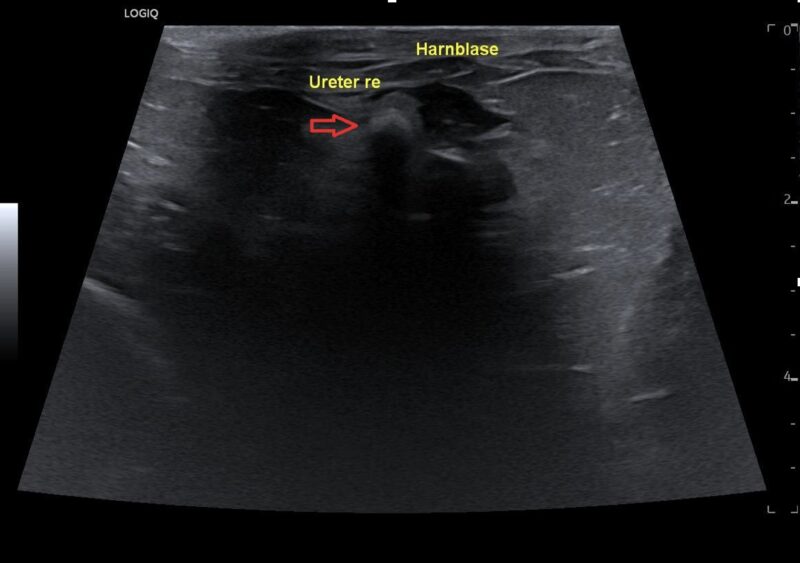

Die Röntgenuntersuchung zeigte eine weichteildichte Masse im rechten mittleren Abdomen sowie eine radiodichte Struktur dorsal der Harnblase. Die Sonographie ergab eine deutlich veränderte rechte Niere mit hochgradiger Hydronephrose sowie eine ausgeprägte Peritonealreaktion. Der rechte Ureter war stark dilatiert mit einer schallschattenbildenden Struktur kurz vor der Einmündung in die Harnblase. Die linke Niere sowie der linke Ureter waren sonographisch unauffällig. Auf Basis dieser Befunde wurde die Diagnose einer hochgradigen rechtsseitigen Hydronephrose sekundär zu einer Ureterolithiasis gestellt.